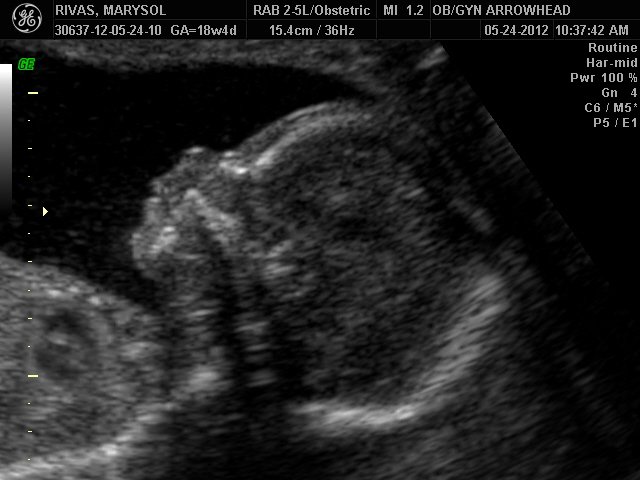

We offer complimentary 3D/4D Ultrasounds to all our OB patients around 30 weeks! The following photos are some examples of our work, shown with permission from our patients.